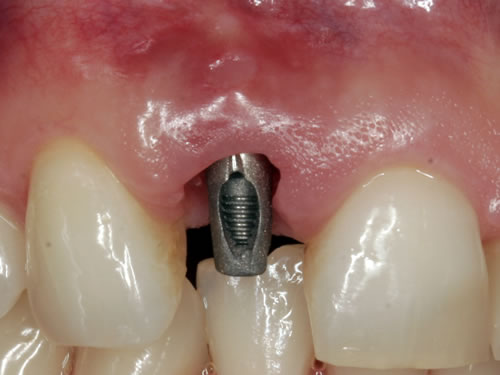

Bei oberen Frontzähnen wird mit bestimmten Freilegungstechniken das Zahnfleisch zur Lippe häufig noch etwas korrigiert. Die Freilegung bietet sich für die Maßnahme an, da zwangsläufig Zahnfleisch und Bindegewebe bei der Eröffnung anfallen (Abb. 8.2 bis 8.4). In die Implantate werden Einheilkappen oder Gingivaformer eingesetzt, damit es in der Abheilungsphase nicht zu einem erneuten Zuwachsen der Schleimhaut kommt.

Abb. 8.3: Eingeschraubter Gingivaformer verhindert das Zuwachsen der Wunde.

Abb. 8.4: Perfekte Weichgewebsverhältnisse.